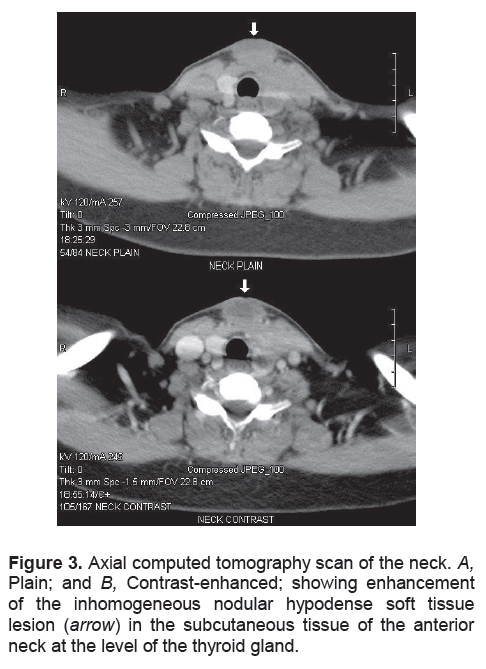

).She was referred to Otorhinolaryngology for incision and drainage of the midline neck abscess. Repeat FNA was uninformative yielding only purulent material. The abscess was then unroofed and drained. Purulent material continued to exude through the sinus at the center of the swelling. A contrast-enhanced computerized tomography (CT) scan of the neck was performed to rule out branchial cleft anomalies. The scan revealed an irregular inhomogeneous soft tissue structure measuring 3.0 cm x 3.4 cm x 2.8 cm with an area of hypodensity suggestive of infective fluid collection above and extending into the thyroid lobe (Figure 3A and 3B). Fistulogram showed a subcutaneous blind-ended pouch with contrast pooling, suggestive of an abscess cavity. No fistulous tract into the pyrifrom sinus or other pharyngeal structures was appreciated (Figure 4). Several courses of oral antibiotics were prescribed during the succeeding weeks but without apparent resolution of symptoms. The lists of antibiotics were: cefixime 200mg tablet every 12 hours for 7 days; ampicillin/sulbactam 750 mg tablet every 8 hours for 14 days plus clindamycin 300 mg tablet every 6 hours for 7 days.

Figure 3. Axial computed tomography scan of the neck. A, Plain; and B, Contrast-enhanced; showing enhancement of the inhomogeneous nodular hypodense soft tissue lesion (arrow) in the subcutaneous tissue of the anterior neck at the level of the thyroid gland.